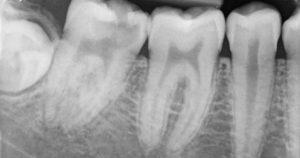

1. Periapical X-rays- Here, the X-ray image taken with the help of a sensor helps in viewing the crown up to the root region including the surrounding bone at the apex in the upper or the lower jaw whichever is targeted. These X-rays help in detecting endodontic and periodontal lesions, tooth decay, bone loss, etc.